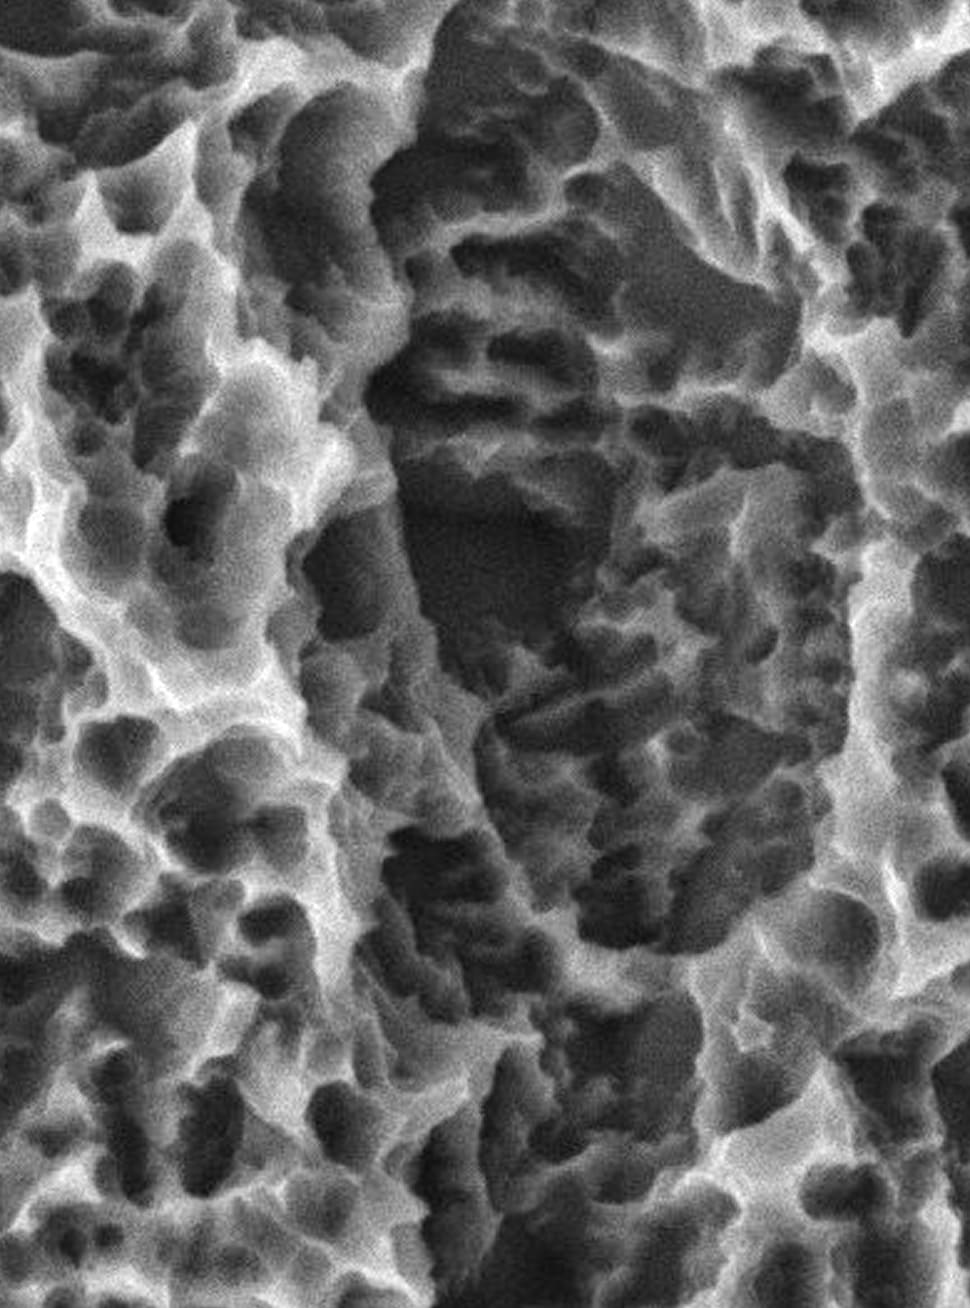

S.L.A表面处理技术经20多年验证